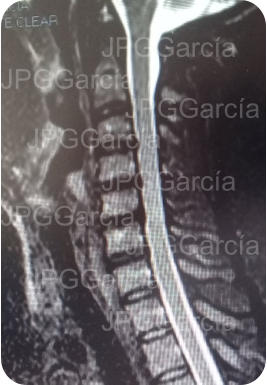

Tratamiento microquirúrgico de hernia extruida cervical con mielopatía

Estudios de control postquirúrgico radiográfico y de resonancia magnética